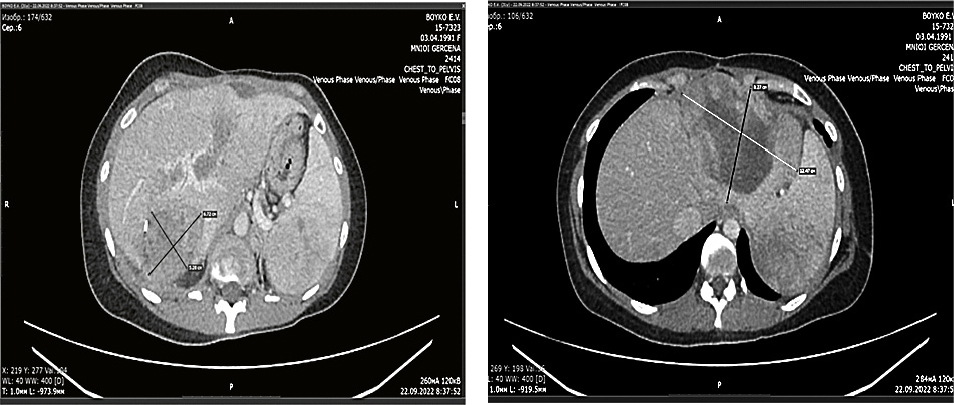

- D14.3. ВМФО нижней доли левого легкого, состояние после R0-анатомической резекции базальных сегментов нижней доли левого легкого, медиастальной лимфодиссекции в 2015 г. Прогрессирование в ноябре 2021 г., забрюшинный солитарный метастаз с врастанием в SI, SVI, SVII сегменты печени, метастаз в SIVb печени (рис. 1).

Рис. 1. КТ грудной клетки, брюшной полости и забрюшинного пространства, таза с внутривенным контрастированием. Ноябрь 2021 г.

Заключение: печень увеличена до 238×142×227 мм, практически всю правую долю занимает неоднородное опухолевое образование. Протоки не расширены. В селезенке опухолевидное образование 46×53 мм. В легких очаговых и инфильтративных изменений не определяется.

Fig. 1. CT scan of the chest, abdomen, retroperitoneum, and pelvis with intravenous contrast enhancement. November 2021.